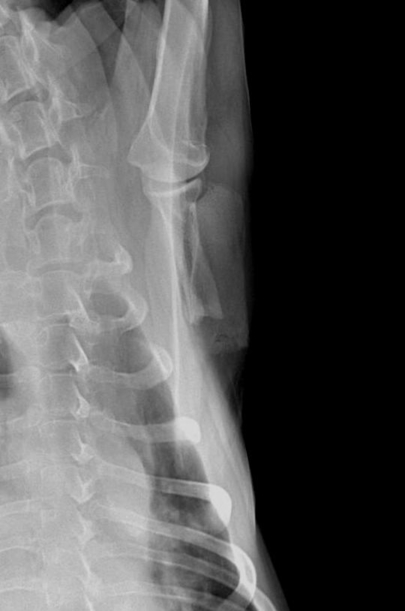

Un examen radiographique est réalisé sur animal vigile. Le coude gauche présente une dégradation arthrosique déjà avancée que l’on retrouve également sur le coude droit. Une déformation des tissus mous est visible en regard de la portion caudale de la scapula. L’articulation scapulo-humérale ne présente pas d’anomalie, seule la scapula présente des modifications de son architecture sur sa face interne avec une corticale effacée, une association d’ostéolyse et d’ostéoproduction (fig. 2 et 3).